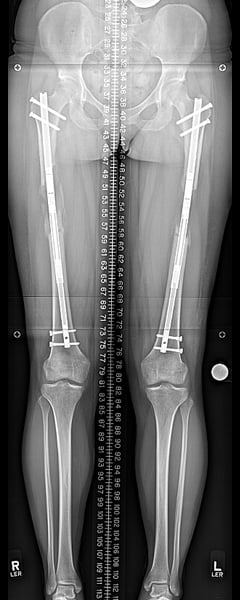

Femurs at end of consolidation.

The most common increase in height is three inches (or 8 cm) because that is how long the implanted rods extend. If the procedure is repeated in the lower leg bone (the tibia), another 2 to 3 inches can be obtained, for a total of about 5 to 6 inches of added height.

Lengthening three inches is approximately a six-month process. Following surgery and short rest period, the bones are lengthened by less than 1mm (less than 0.04 inches) per day, and the lengthening portion of the treatment takes 3 to 4 months. The bones then take another 6 to 8 weeks to heal and then normal activity can resume. The lengthening rods are removed around 12 months after the initial surgery.